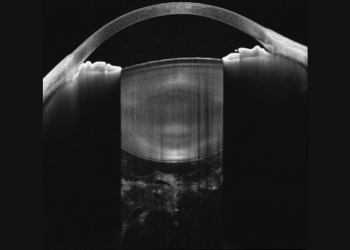

Anterior segment imaging with VG-200I